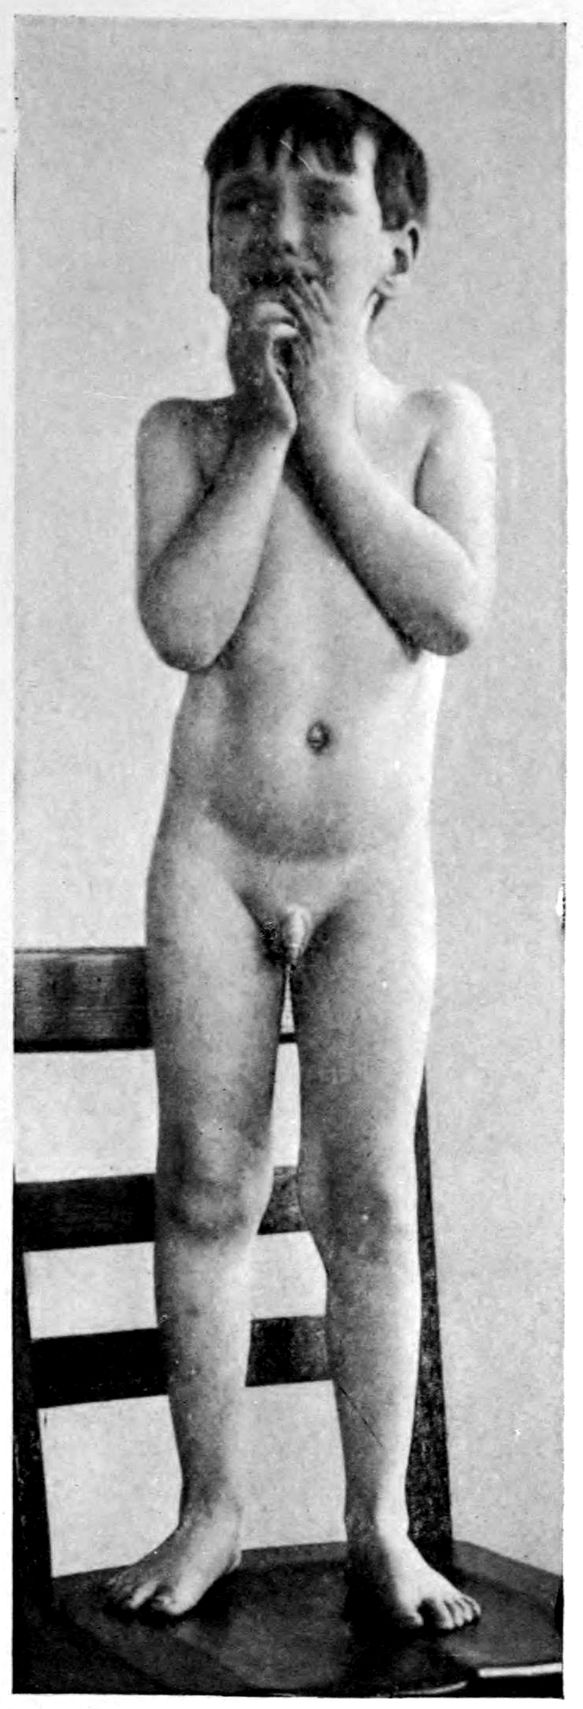

JUVENILE PARETIC NEUROSYPHILIS (“juvenile paresis”). Autopsy.

Case 5. John Lawrence was an under-sized negro, who came under hospital observation when he was 23 years of age. There was some evidence that the patient’s father was a neurosyphilitic although accurate data were out of the question. At all events, John had Hutchinsonian teeth, a forward bowing of the tibiae, and Argyll-Robertson pupils. These findings together with a history of backwardness at school seem to stamp the diagnosis. It seems that there had been a change for the worse from the age of 18, though the boy had been able to sell newspapers and black shoes up to within a year of his arrival at the hospital. During the last months of his life, he showed a general incoördination, with false movements suggesting those of a drunken person. There were numerous tremors, the glance was shifting, and there was a tendency to nystagmus. Some of these phenomena (taking into account that the Hutchinsonian teeth were not entirely typical and there was even at times some doubt as to whether the pupils were actually stiff) led to a question of the diagnosis multiple sclerosis.

There was, however, little doubt that the case was one of juvenile paresis. Among the symptoms found at various times in this case are the following: disorientation for time, place and persons, confusion, with coarsely irrelevant replies to questions, ill-defined and transitory delusions of persecution, auditory, tactile, and visual hallucinations, and defective memory.

Early in life, the patient had had a habit of falling asleep in school hours, and had experienced a number of falls at various times. During an attack of measles he had had a number of spasms, each of which lasted ten minutes or more.

The autopsy showed death to be due to an early bronchial pneumonia. The thymus was persistent, measuring 3 × 2 × .5 cm. The marrow of the femur was red.

46There was a moderate degree of sclerosis of the aorta confined to a few plaques in the arch (not a characteristic syphilitic scarring of the aorta). The spleen was small and had a thickened capsule.

The majority of the lesions, however, were in the nervous system, and the following description is taken from the routine hospital records to exemplify the findings in a fairly characteristic case of Juvenile Paresis.

Head: Scalp closely adherent to calvarium. Calvarium heavy without diploë. Dura adherent to calvarium in bregmatic region. Sinuses contain liquid blood. Arachnoidal villi in considerable quantity. Pia mater contains considerable clear fluid and shows diffuse haziness and focal thickenings. The diffuse haziness is almost universal and is best marked over the superior surface of the cerebellum. The focal thickenings are of general distribution over the veins of the sulci on the superior surface of the brim and are heaped up to form considerable linear mounds near the region of the arachnoidal villi. The superior surface of the cerebellum is traversed by similar linear mounds of fibrous tissue running at an angle to the laminæ. There is no notable increase of fibrous tissue at the base.

Brain: Weight 965 grams. The sulcation is roughly symmetrical except in the occipital poles where there is unusually rich and complex but shallow sulcation. The cortical substance is everywhere firmer than normal, but the sulci fail to flare notably. In a few places there is a focal increase of consistence of still greater degree with apparent local hypertrophy (or gliosis with increase of substance). These foci are in the right second temporal gyrus (3 cm. in diameter) and in the left first temporal gyrus (of same size but somewhat less firm) and are of a whitish, waxen appearance, being visible several feet away by reason of their color and apparent encroachment upon the adjacent sulci. The foci are sharply limited by the sulci laterally, but pale out gradually before and behind.

The convolutions of the vertex show another type of lesion. The tissue of the greater part of the vertex resembles that of the flanks and base in being firmer than normal and of a grayish pink color. Behind the fissure of Rolando on the right side and behind the anterior limits of the ascending frontal region on the left 47side the brain tissue of the vertex becomes suddenly still firmer and of a yellowish gray color. This lesion disappears gradually into the occipital microgyria behind and the gyri gradually lose their yellowish tint. The lesion fades away gradually so that it fails to involve the temporal convolutions.

The cerebral tissue cuts firmly and smoothly. The tissue of the frontal region is a little edematous. The white matter is of a normal appearance. The ependyma of all the ventricles is somewhat sanded. The fourth ventricle is most affected.

The cerebellum is not edematous and is as firm as the normal olivary bodies. The cerebellar hemispheres are symmetrical and of a normal appearance, save that the laminæ are slightly narrower than usual and very compactly set. The color, where not obscured by the haziness of the pia mater, is of a grayish pink somewhat suggestive of freshly tanned shoe leather. The substance cuts smoothly and firmly. The dentate nuclei are unusually firm. The pons is small, but of the usual color. Lower structures normal except the cord which is small and shows curious deviations from the normal markings. The posterior horns and gray commissure are at many levels the only structures to preserve the normal gray appearance, so that the H or butterfly appearance is replaced by a crescent. At these levels, traces of gray matter often stand out in the loci of the anterior horns.

The important anatomical diagnoses in the nervous system are as follows:

Atrophy of cerebrum, 965 grams (there is of course a question whether we are not dealing with a degree of cerebral hypoplasia).

Focal scleroses of cerebrum, suggesting the tuberous scleroses of Bourneville.

Occipital microgyria.

Cerebral and cerebellar gliosis.

Chronic ependymitis.

Gliosis of the gray matter of the spinal cord.

Chronic diffuse and focal leptomeningitis.

The microscopic examination confirmed the diagnosis of paresis. The hypertrophic nodules were of special interest. 48They were found to be overlain by a characteristic though thin exudate of lymphocytes and plasma cells, together with pigmented cells. The nodules appeared to be supplied with an unusual number of vessels of small calibre, about which were a few lymphocytes. The large vessels and those with well developed adventitiæ were surrounded by more numerous lymphocytes and by more focal accumulations of pigmented cells. The cortex in the middle of a nodule had almost lost its characteristic cortical layering. The cortex was here reduced (specimen from temporal lobe) to about one-quarter of its normal thickness, and was found to be composed largely of expanded neuroglia cells and vascular tissue, with a few nerve elements, small, shrunken, and dark-staining. The destructive process appeared to have borne hardest on the layer of internal large pyramids and the fusiform layer. There was, however, nowhere any evidence of focal necrosis such as ought to characterize a true gumma. The sections stained by the Marchi method failed to show evidence of fatty degeneration within the focus, although there was a marked diffuse accumulation of fatty granulations along the nerve fibres in the underlying white matter. A special study of the cerebellar material was made by one of the authors.[4] Occasional Purkinje cells showed the characteristic binucleate condition, which has frequently been noted in recent literature.

The cerebellum of this case was perhaps the most markedly diseased of all portions of the nervous system. As noted, the cerebellar tissue was exceedingly firm. How far the notable incoördination of the case (he was observed on staff rounds characteristically curled up in a heap, showing quite an unusual degree of general incoördination) was due to the cerebellar lesions, it is perhaps not possible to say.

Summary: John Lawrence, Juvenile Paretic Neurosyphilis, is a foil to Case 3 (James Dixon), paretic neurosyphilis due to acquired syphilis.

Both showed Cerebral Atrophy, but Lawrence the more 49markedly because of hypoplasia incidental to the congenital origin of his condition.

Whereas Dixon gave little or no sign of stigmata, Lawrence (besides being under-sized, having suspicious teeth, and showing at autopsy a persistent thymus) showed a Hydromyelia and curious trefoil shape to the spinal cord. Dixon on the other hand had liver lesions and arterial lesions of the leg.

The suggestion of Tuberous Sclerosis in Lawrence is not found in Dixon; but we have not found it elsewhere. Bourneville did not describe tuberous sclerosis as syphilitic.

Binucleate Purkinje cells emphasize the congenital source of the lesions in Lawrence.